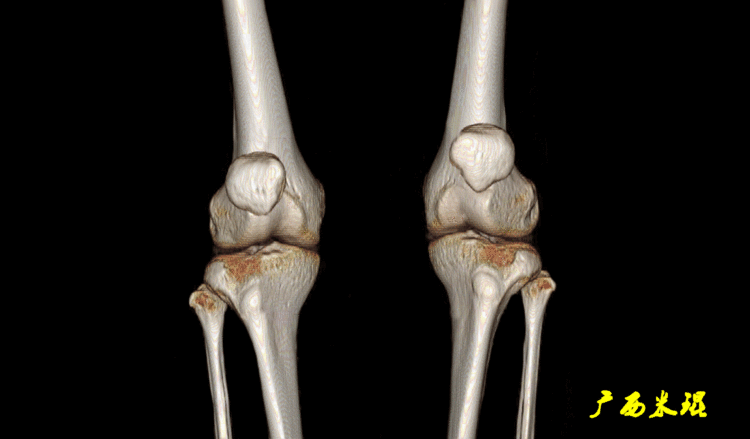

髌骨脱位的病人在10至17岁时最常见,女性居多,经常有自身的解剖异常,所以双侧发病多见,常见的原因有全身多关节松弛症、Q角过大、股骨滑车异常、高位髌骨、膝外翻及/或膝过伸等,这些需要我们在诊查病人中认真的进行检查和观察。

同时注意下肢力线的检查,是否有膝外翻以及膝关节过伸,这些体征都对髌骨脱位有着重要的影响,而且在这基础上还要进行站立位全长片的检查。

DR检查包括下肢全长正位片、侧位片、膝关节正侧位、髌骨切线位等,有助于评估膝关节力线及滑车的形态,髌骨高度、髌骨倾斜,关节病等信息。